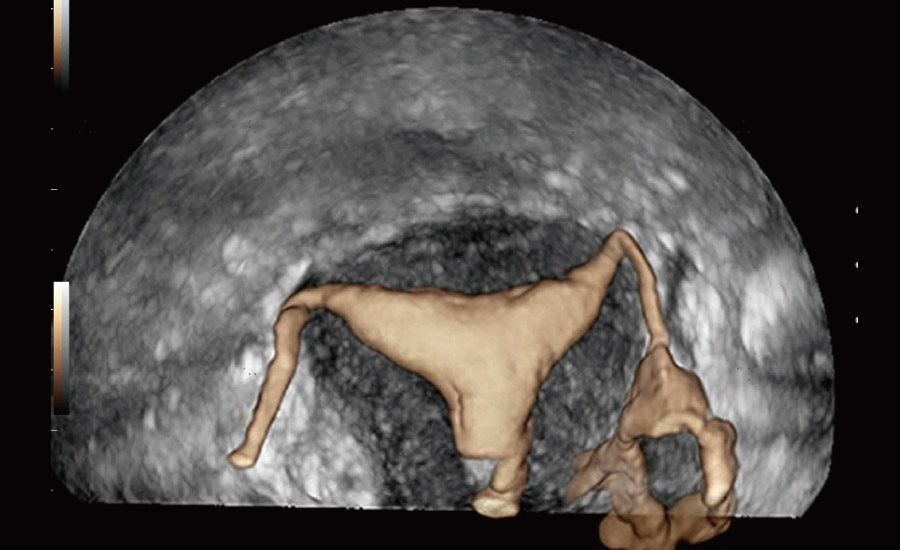

UMA (Ultra-Micro Angiography)

The innovative technology breaks the bottlenecks of traditional Doppler imaging. With ultra-high spatial resolution and flow sensitivity, it allows detecting super-subtle and super-slow flow perfusions, thereby extending the clinical application of qualitative and quantitative ultrasound evaluation in fetal brain, kidney, placenta, endometrium, ovary, etc.

Combining advanced algorithms and domain-specific knowledge, the innovative Smart Scene solution enables auto identification of tissue characteristics and provides organ-specific diagnosis with full-stack intelligence. Based on auto scenario identification, the solution not only realizes smart 2D scanning with auto settings and measurements, but also delivers 3D full-stack intelligence in every step from volume imaging optimization to the difficult 2D plane acquisition, and quantification throughout whole procedure. It helps a lot in reducing the dependency on clinical skills, while increasing diagnostic accuracy, confidence and efficiency.